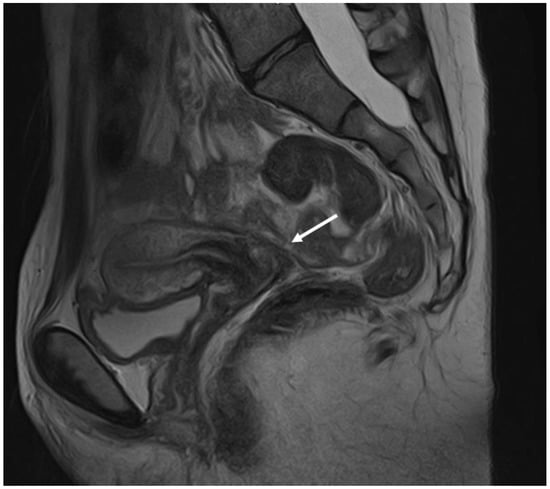

3.1. Ovarian Endometriosis

3.3. Deep Endometriosis